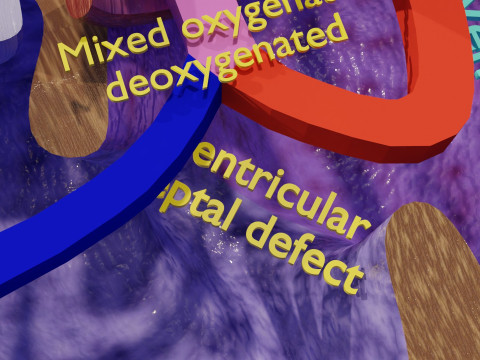

The model meshes include adult circulation versus circulation in Tetralogy of Fallot (TAF), arrow labels and text labels. The blood flow in a patient with Tetralogy of Fallot is outlined in this model. To contrast it to normal blood circulation a separate model of normal circulation is included. The Tetralogy of Fallot (OVER RIDING OF AORTA, PUL STENOSIS, VENTRICULAR SEPTAL DEFECT, RIGHT VENTRICULAR HYPERTROPHY), fossa, ligament teres , venosus, and arteriosus are duly depicted with proper labelling and blood flow directional arrows. Excellent model for teaching, demonstration and knowlegde of human body. The models include both procedural and image textures blend files separately. The texture file include diffuse, roughness and normal png and jpeg based on non overlapping UV maps.